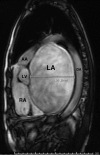

An Audaciously Aneurysmal Atrium

Keywords: Echocardiography; Imaging; Mitral stenosis; Rheumatic heart disease.